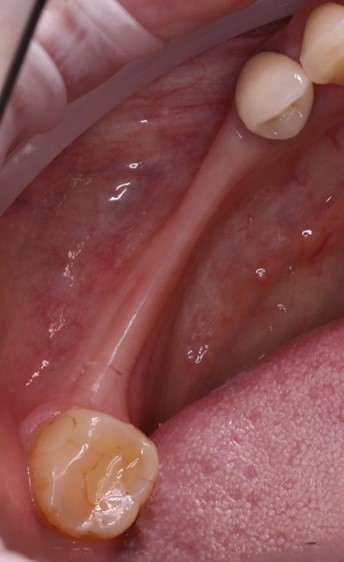

Поэтому после удаления зуба мы ждём, в общей сложности, около 4-8 недель, затем приступаем к имплантологическому лечению. Хотя, иногда бывают ситуации, когда мы делаем синуслифтинг одномоментно с удалением зуба, а сам имплантат ставим попозже:

через 4 месяца: